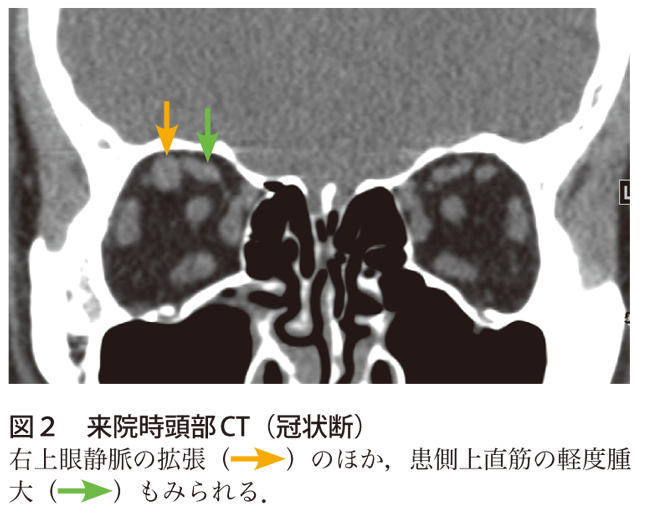

て,右内頸動脈海綿静脈洞瘻が疑われ同日緊急入院 となった。 初診時所見:意識清明で体温3 度であった。 視力は右05 左09 と右視力低下を認めた。右眼球 突出,右上眼瞼発赤・腫脹を認め(図1),開眼は 臨床 副鼻腔炎に続発した海綿静脈洞血栓症の1 例る深部の静脈洞血栓になりまして、こ の場合は意識障害が進行することもあ ります。 齊藤 視力障害などもあるのですか。 伊澤 海綿静脈洞血栓症の場合は目 の痛み、眼球突出、眼瞼浮腫、眼球運 動障害、このようなものも出てきます副鼻腔炎から海綿静脈洞血栓症,髄膜炎を併発し急激に失明に至った1症例 Loss of vision in a case of sinusitis with secondary cavernous sinus thrombosis and meningitis 小嶌 美恵子 1, 兜坂 法文 1, 和田 公平 2, 深尾 篤嗣 3 Mieko Kojima 1, Norifumi Tosaka 1, Kouhei Wada 2, Atsusi Fukao 3 1

右海綿静脈洞から蝶形頭頂静脈洞,一部眼窩にかけて高信号域を認めた. 表1 有痛性眼筋麻痺の原因疾患3)一部改変 血管障害 脳出血,くも膜下出血,下垂体卒中,脳動脈瘤,糖尿病性眼筋麻痺 (痛みは稀),ccf,海綿静脈洞血栓症化膿性海綿静脈洞血栓症,細菌性髄膜炎を来たしたLemierre症候群 52:7 Fig 1 Eye movement of the patient His right eye showed slight exophthalmos and swelling of the eyelid Lateral and inferior gaze of his right eye movement was disturbed Fig 2内科学 第10版 脳静脈洞血栓症・脳静脈血栓症の用語解説 概念 脳静脈洞が種々の原因による血栓で閉塞され頭痛などの脳圧亢進症状をきたすもので,血栓が静脈洞から脳表静脈に及ぶと脳局所症状を呈する.病変は脳静脈洞の血栓性閉塞が主体であるが,脳表静脈に血栓が進展した場合には